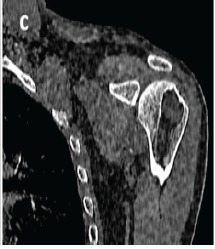

Symptomatic Fatty Involution of a Simple Bone Cyst in the Proximal Humerus: A Rare Case Report

Arun Krishnamoorthi , Silambarasi Nagasamy